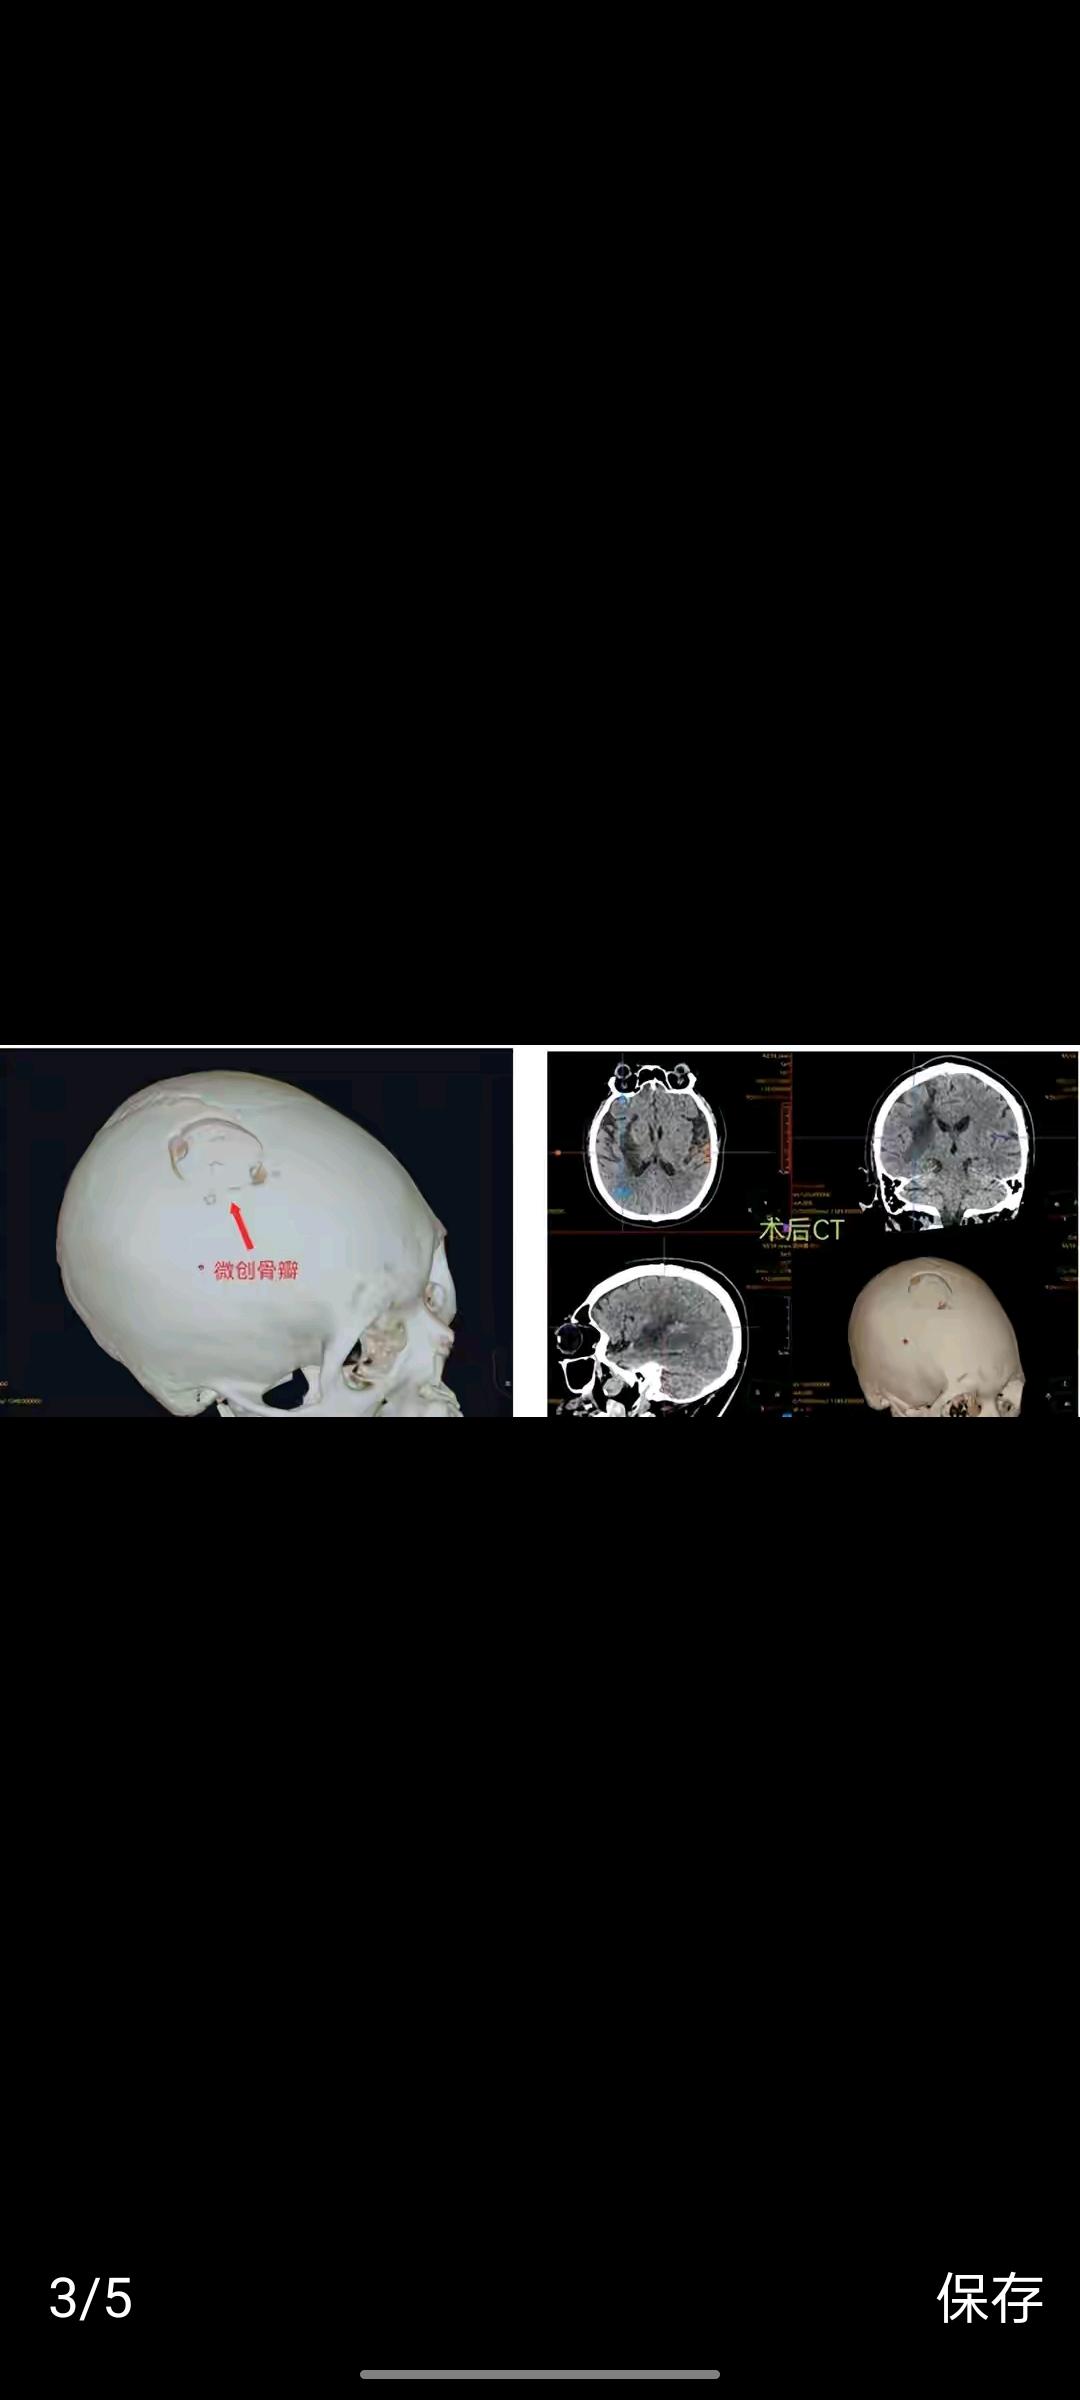

万幸的是,医疗科技的光,照亮了他的重生路。医生团队借助高精度医疗机器人,精准定位颅内血肿,规划出最优治疗路径,避开关键神经与血管,以最小的创伤完成手术,后续又通过康复机器人辅助他开展系统性训练。从卧床不起到重新站立,从无法动弹到肢体功能逐步恢复,机器人不仅帮他挣脱了病痛的枷锁,更守住了一个濒临破碎的家庭。